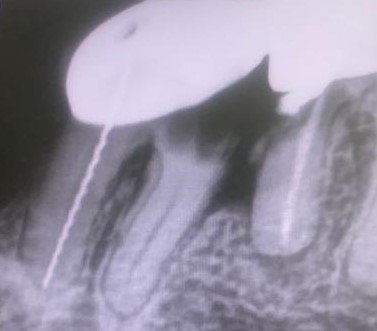

La técnica quirúrgica para este menester es parecida a una apicectomía, pero en lugar de quitar solo el ápice radicular quitamos toda la raíz dental. Así pues lo que se hizo fue extracción de la raíz distal del primer molar y extracción de la raíz mesial del segundo molar. Con lo que la prótesis sigue teniendo dos pilares.

En conclusión, lo que hicimos fue alisar la prótesis por debajo de forma que quede higiénica y por tanto no retenga restos. La técnica quirúrgica quedo muy bien. El tiempo de inflamación de la cara es como si se hubiera hecho la extracción de la muela del juicio, pero una vez se va la inflamación el paciente sigue haciendo vida normal, como el día que se le puso la prótesis.

Lo más importante, es que a los diez días se quitan los puntos y poco a poco se vuelve a la normalidad.

Con la secuencia de imágenes se comprende muy bien la técnica quirúrgica realizada.